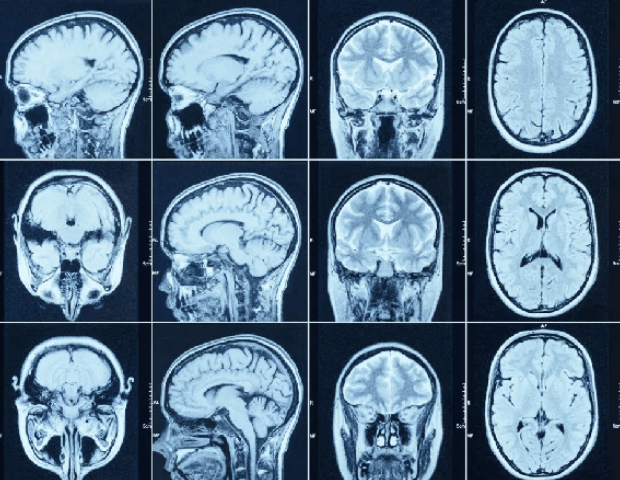

Brain CT scans can provide more detailed information about brain tissue and brain structures than standard X-rays of the head, thus providing more data related to injuries and/or diseases of t...